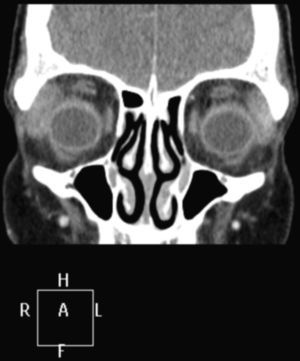

Se solicitó resonancia magnética cerebral, en la que se objetivó un aumento del tamaño de la glándula lagrimal derecha, con afectación supraciliar y orbitolateral superior del ojo derecho, compatible con dacriocistitis / proceso infiltrativo (fig. 1, corte coronal), por lo que es diagnosticada de pseudotumor orbitario con afectación muscular y dacriocistitis, iniciándose corticoterapia a altas dosis y antibioterapia intravenosa, dada la gravedad del proceso. Se realiza una biopsia de la zona inflamada, pero el resultado no es significativo e ingresa para control de la evolución y respuesta a la medicación pautada, dada la gravedad de la afectación ocular.